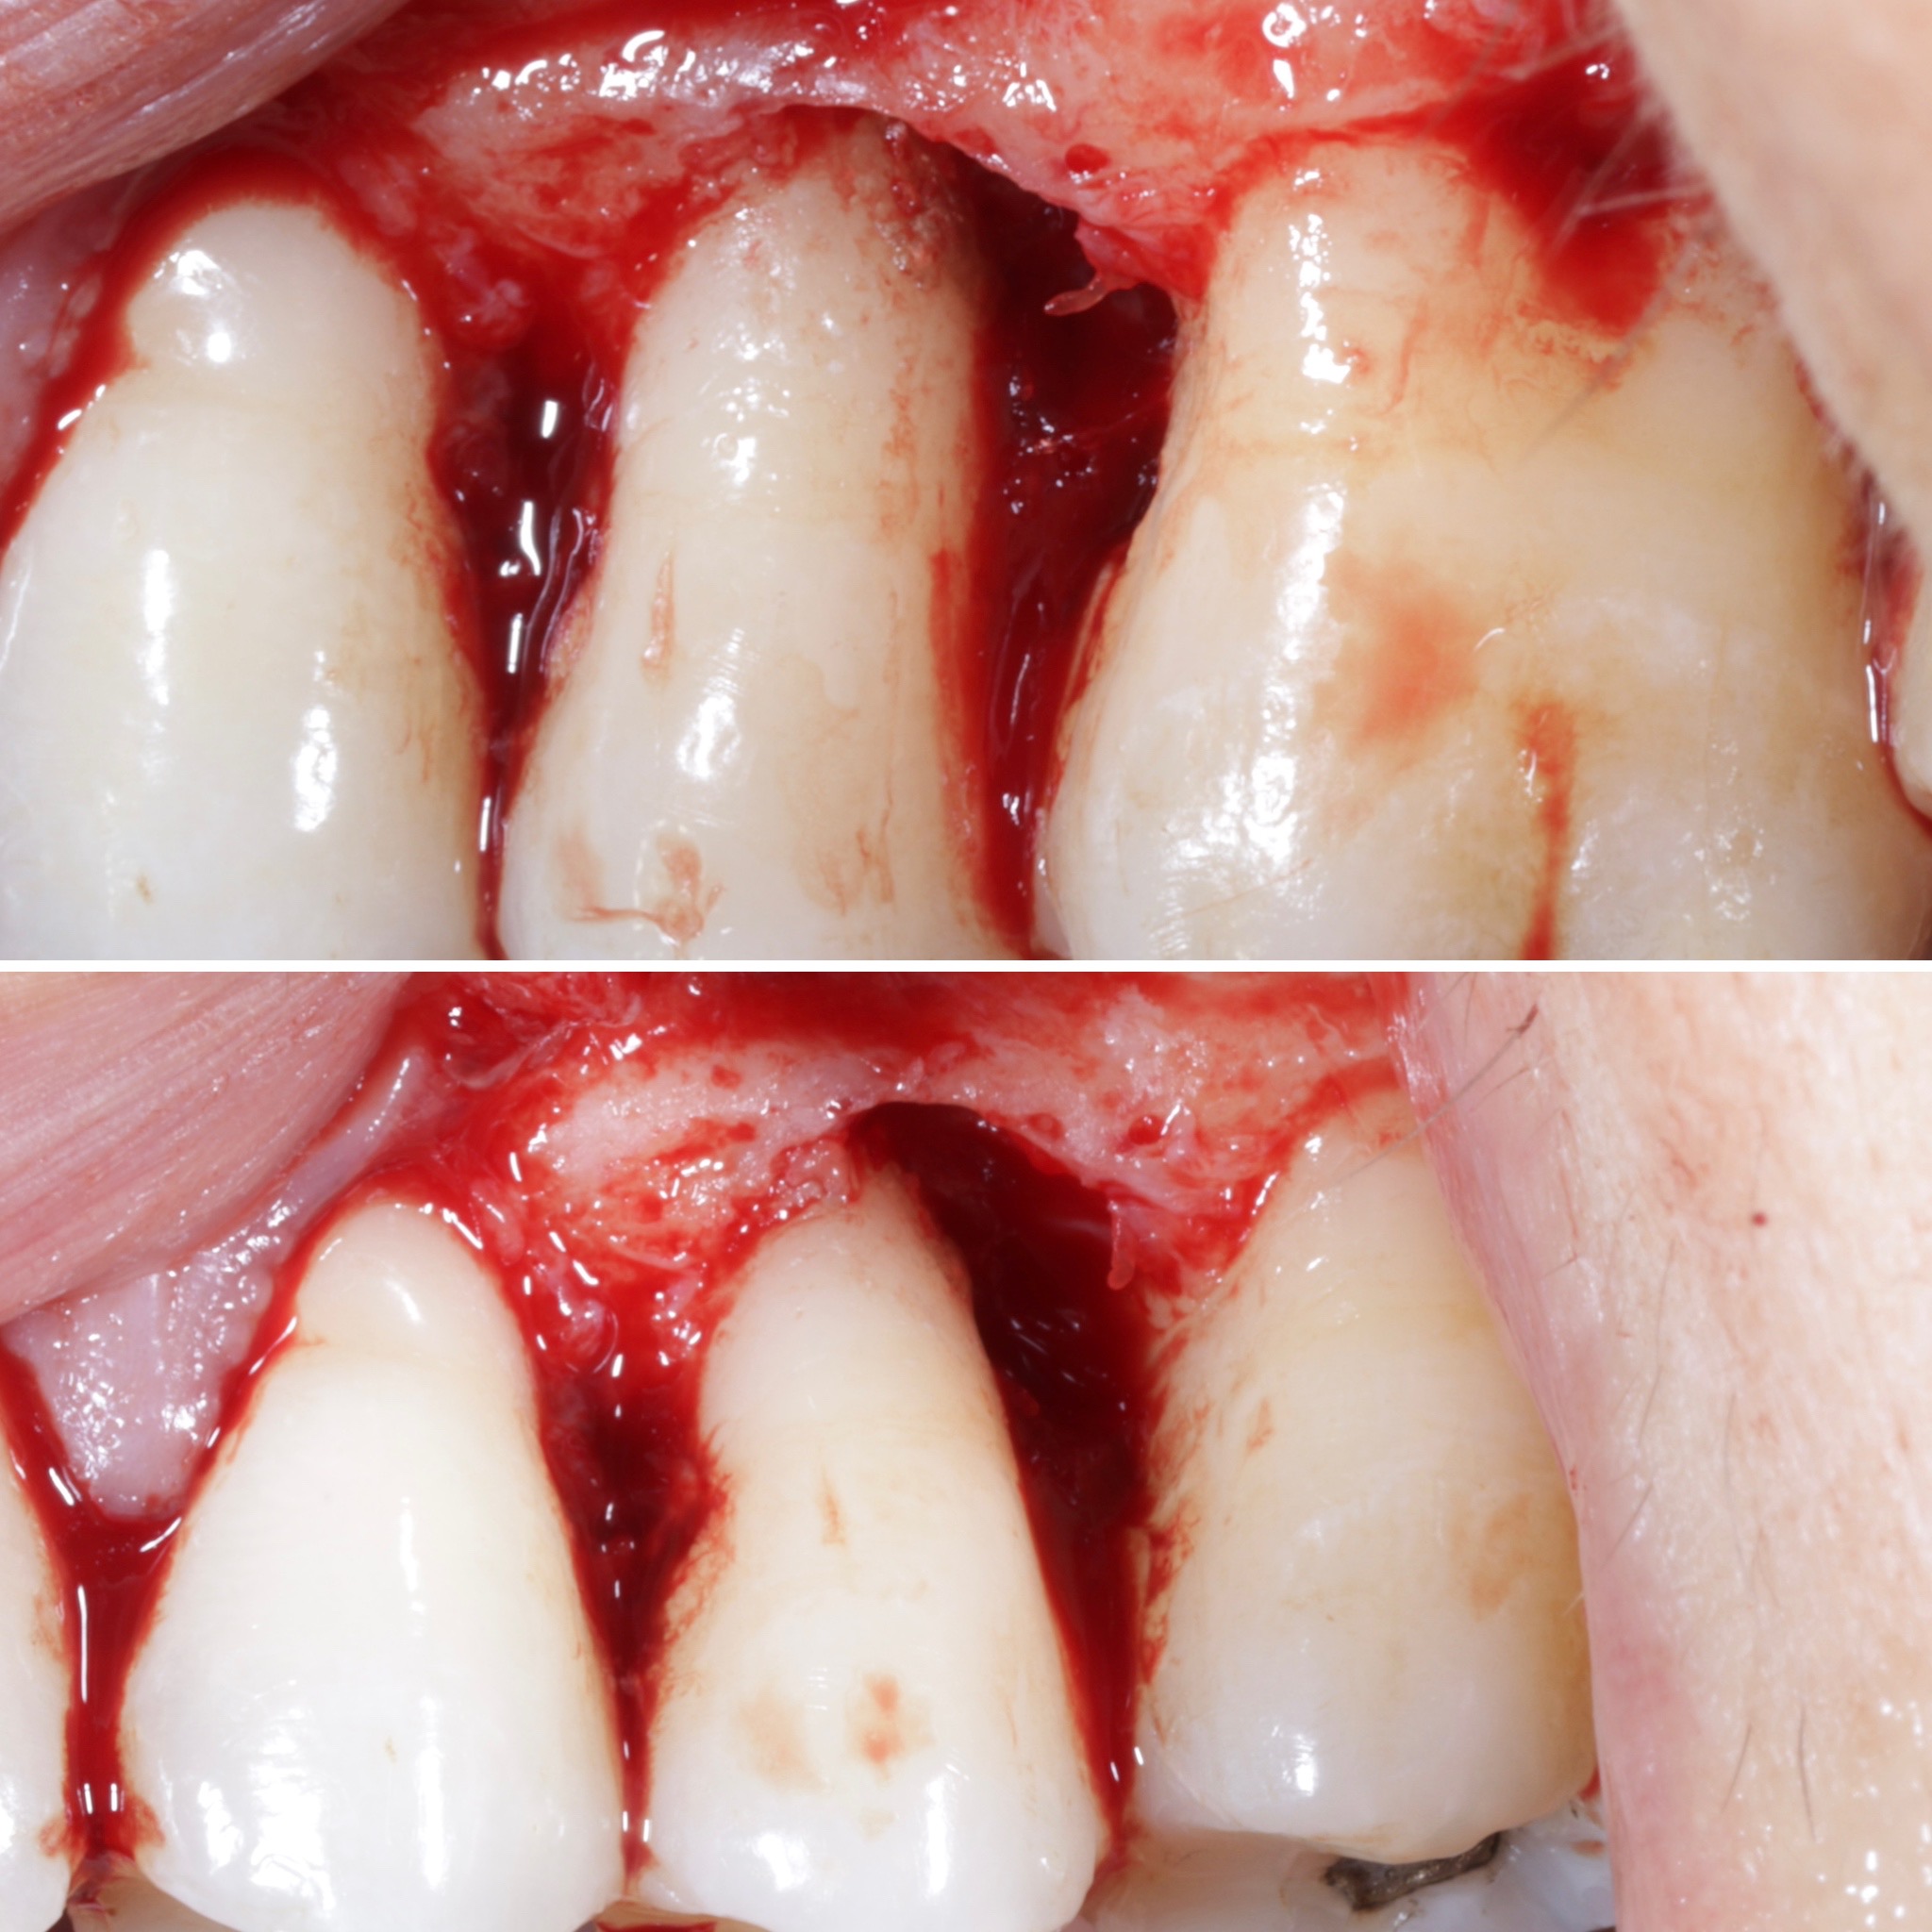

La formación comenzará con la presentación del caso clínico que se abordará durante el curso, seguida de una cirugía en directo, que permitirá observar paso a paso el procedimiento y la toma de decisiones clínicas. Durante la jornada se profundizará en los conceptos biológicos aplicados a

El curso comenzará con la presentación del caso clínico que se abordará durante la formación, seguida de una cirugía en directo. A lo largo de la jornada se desarrollarán conceptos biológicos aplicados a la regeneración ósea, la exposición de casos clínicos centrados en la regeneración